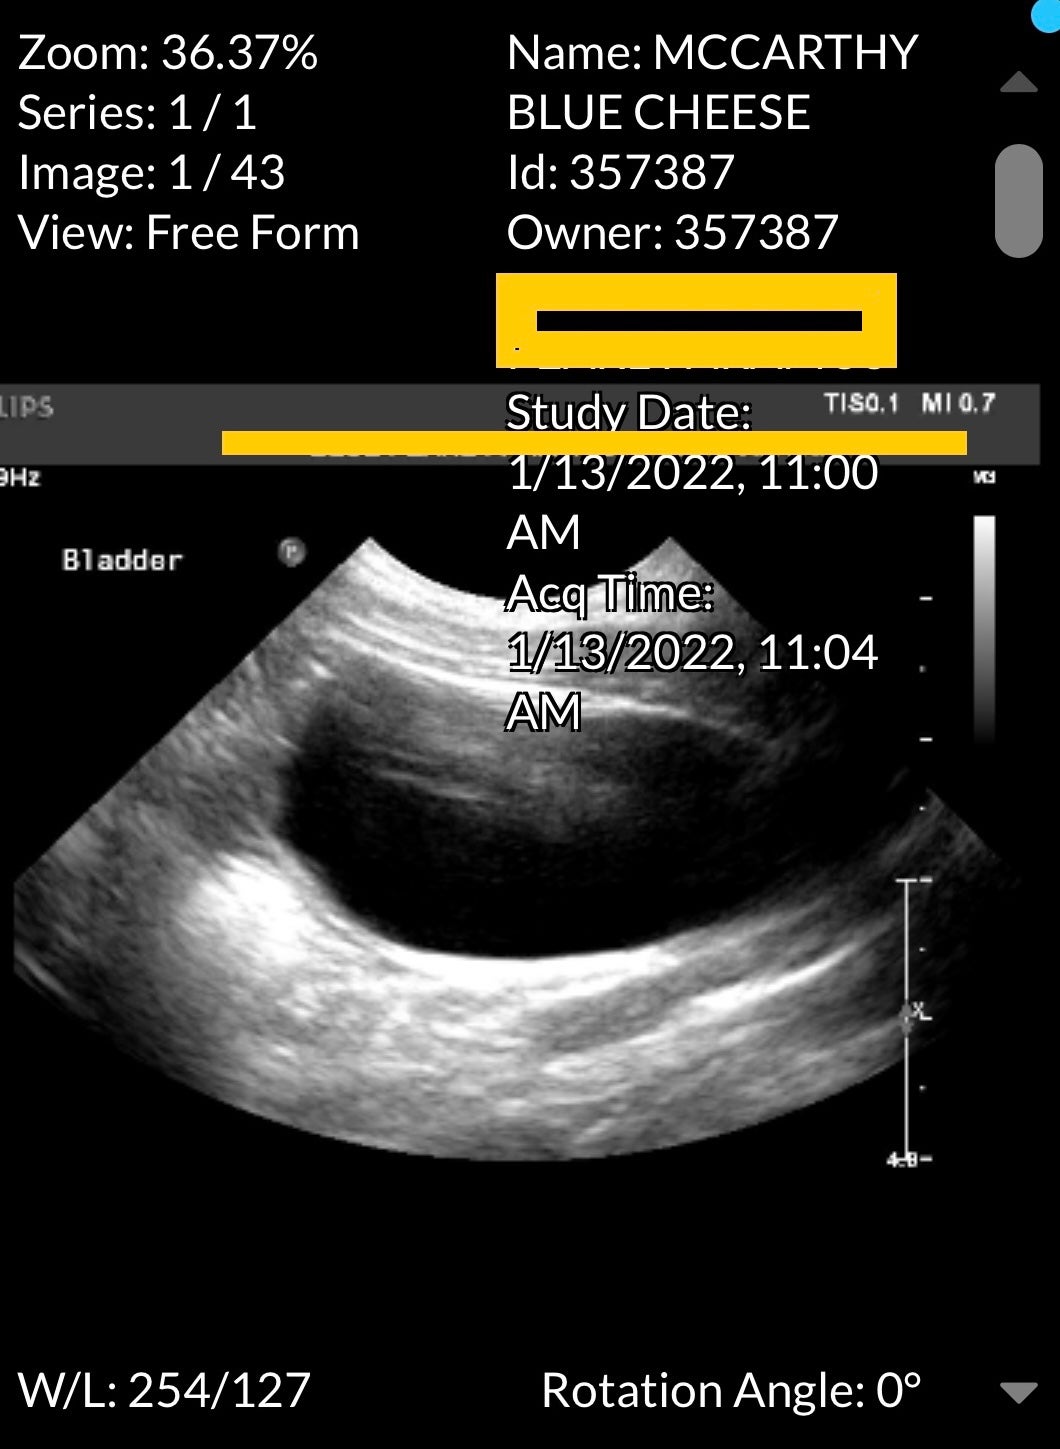

Then giving me a follow-up ring to inform me that the bloodwork found a spike in white blood cells that warranted an ultrasound that would increase my bill to now $1,500 was equally an easy call for the doctor's office to make… Particularly because they didn't have to do it face-to-face.

"White blood cells"?!?!… Shit, that sounds serious. So I blindly agreed to the next procedure and its increased cost.

Four hours later, I received a third faceless call from the office and I was informed that they found a "material blockage" somewhere in my dog's stomach that was preventing her from eliminating waste.

It may have been caused after the vomiting Tuesday night or from the irritation caused by the Advil, but it also might be due to the fact that her breed is simply prone to gastro issues.

I breathed a sigh of relief because this blockage was much less dire than any kidney damage, and during my euphoria, the doctor informed me that in order to remove the blockage, Blue Cheese would have to spend the next 24 hours under their care.

And the new cost of her visit would balloon from $1,500 to $4,300.